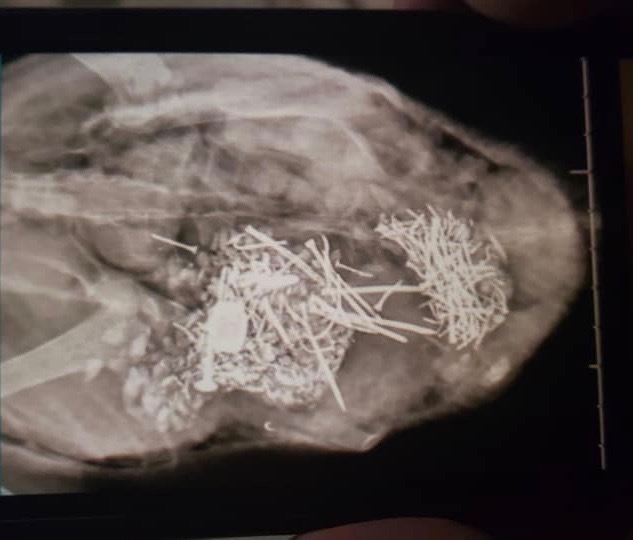

Pica

Bitchin’ Chickens: In people, pica is used to describe compulsive eating of non-food items, such as ashes, clay, and flaking paint. It’s mostly seen in young children or adults with intellectual and developmental disabilities. Pica involving eating dirt may be related to an iron or zinc deficiency. Poultry that eat foreign objects can suffer impaction, perforation of the digestive tract or metal toxicity.

Dr Bowes: This is a case of pica which has several implications: punctures from the sharp nails and screws, and zinc or lead poisoning from the metals. It’s great that the owner had an x-ray done to determine what was going on, but this issue won’t be remedied without surgical intervention. I would be curious what the environment was like that the duck had access to that many metal objects, why it was attracted to eating them and what were its symptoms that required a visit to the vet?